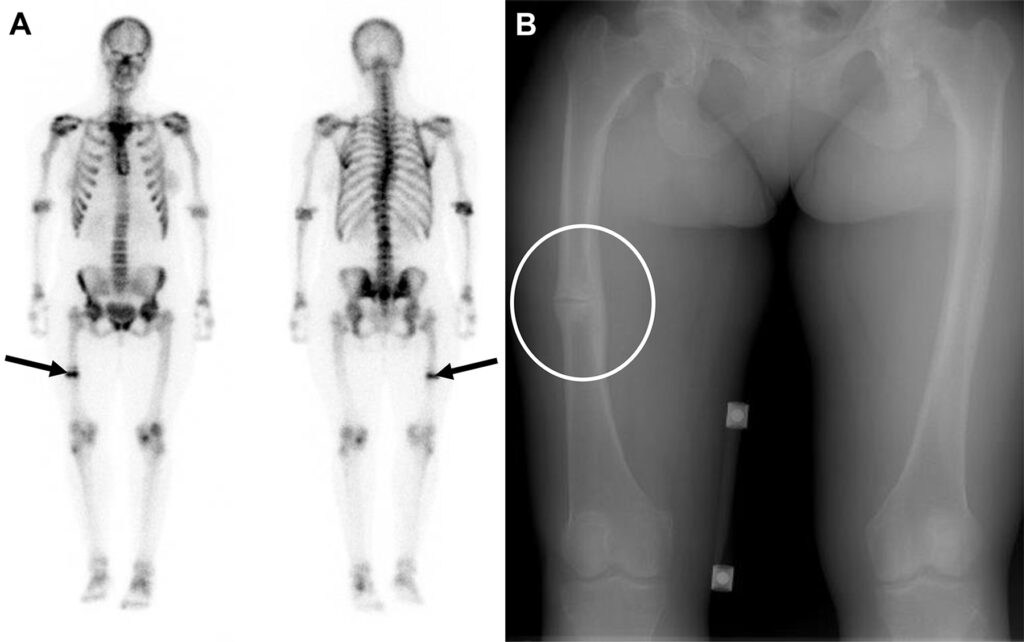

Metastasi da osteosarcoma in un uomo di 22 anni, a cui è stato recentemente diagnosticato un osteosarcoma del femore prossimale destro.

Oltre alla massiva e attesa ipercaptazione nella sede del tumore primitivo, lo studio whole-body rivela una captazione extra-ossea focale e intensa a livello dell’emitorace sinistro.

L’imaging morfologico conferma la presenza di un nodulo polmonare nel lobo superiore sinistro, caratterizzato da calcificazioni periferiche.

Le metastasi derivanti da tumori formanti osso, come l’osteosarcoma, mantengono la capacità osteogenica della lesione primaria. Esse producono matrice osteoide che calcifica, captando avidamente i radiotraccianti osteotropi (come il 99mTc-MDP) e rendendo le metastasi polmonari o dei tessuti molli ben visibili alla scintigrafia ossea.